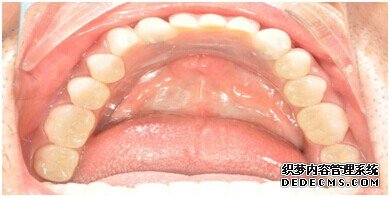

刘女士牙齿拍片初步检查

整个种植牙完成后的效果图